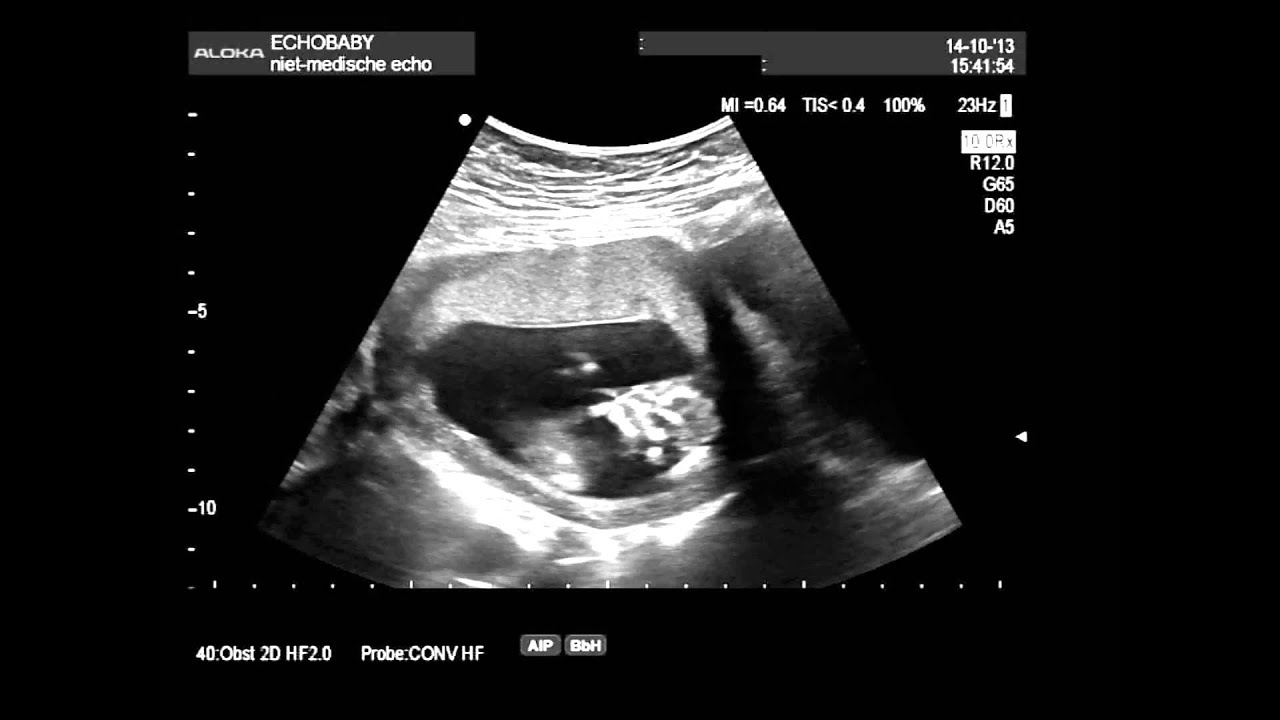

Rond de 10-13 weken krijg je een echo om te bepalen hoe lang je zwanger bent: de termijnecho.. Over de 13 wekenecho. Vanaf 12 weken en 3 dagen tot en met 14 weken en 3 dagen zwangerschap kun je een 13 wekenecho laten maken. De echoscopist kijkt met een echoapparaat naar de schedel, het hart, de buik, de armen en benen en de wervelkolom.. 13-weken echo. Vanaf 1 september 2021 is het mogelijk om de 13 weken echo te laten verrichten. De 13 wekenecho is, net als de 20 wekenecho, een onderzoek naar lichamelijke afwijkingen. De 13 wekenecho kan alleen plaatsvinden in de periode 12+3 tot en met 14+3 weken van je zwangerschap. Sommige (ernstige) afwijkingen zijn al te zien bij 13 weken.